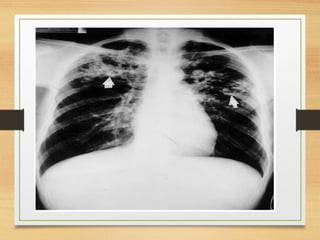

PNEUMONIA

Fisiopatologia

Sinais e sintomas: